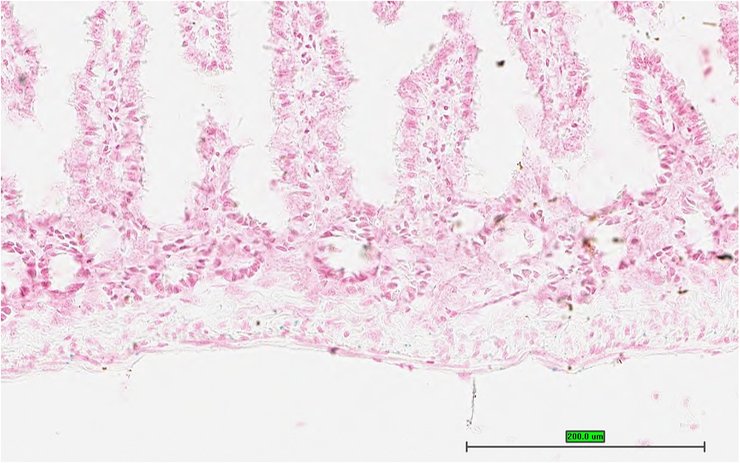

TS28: bladder Present UC Davis_1860100

TS28: bladder Present UC Davis_1860101

TS28: bladder Present UC Davis_1860125

TS28: bladder Present UC Davis_1860126

TS28: bladder Present UC Davis_1860147